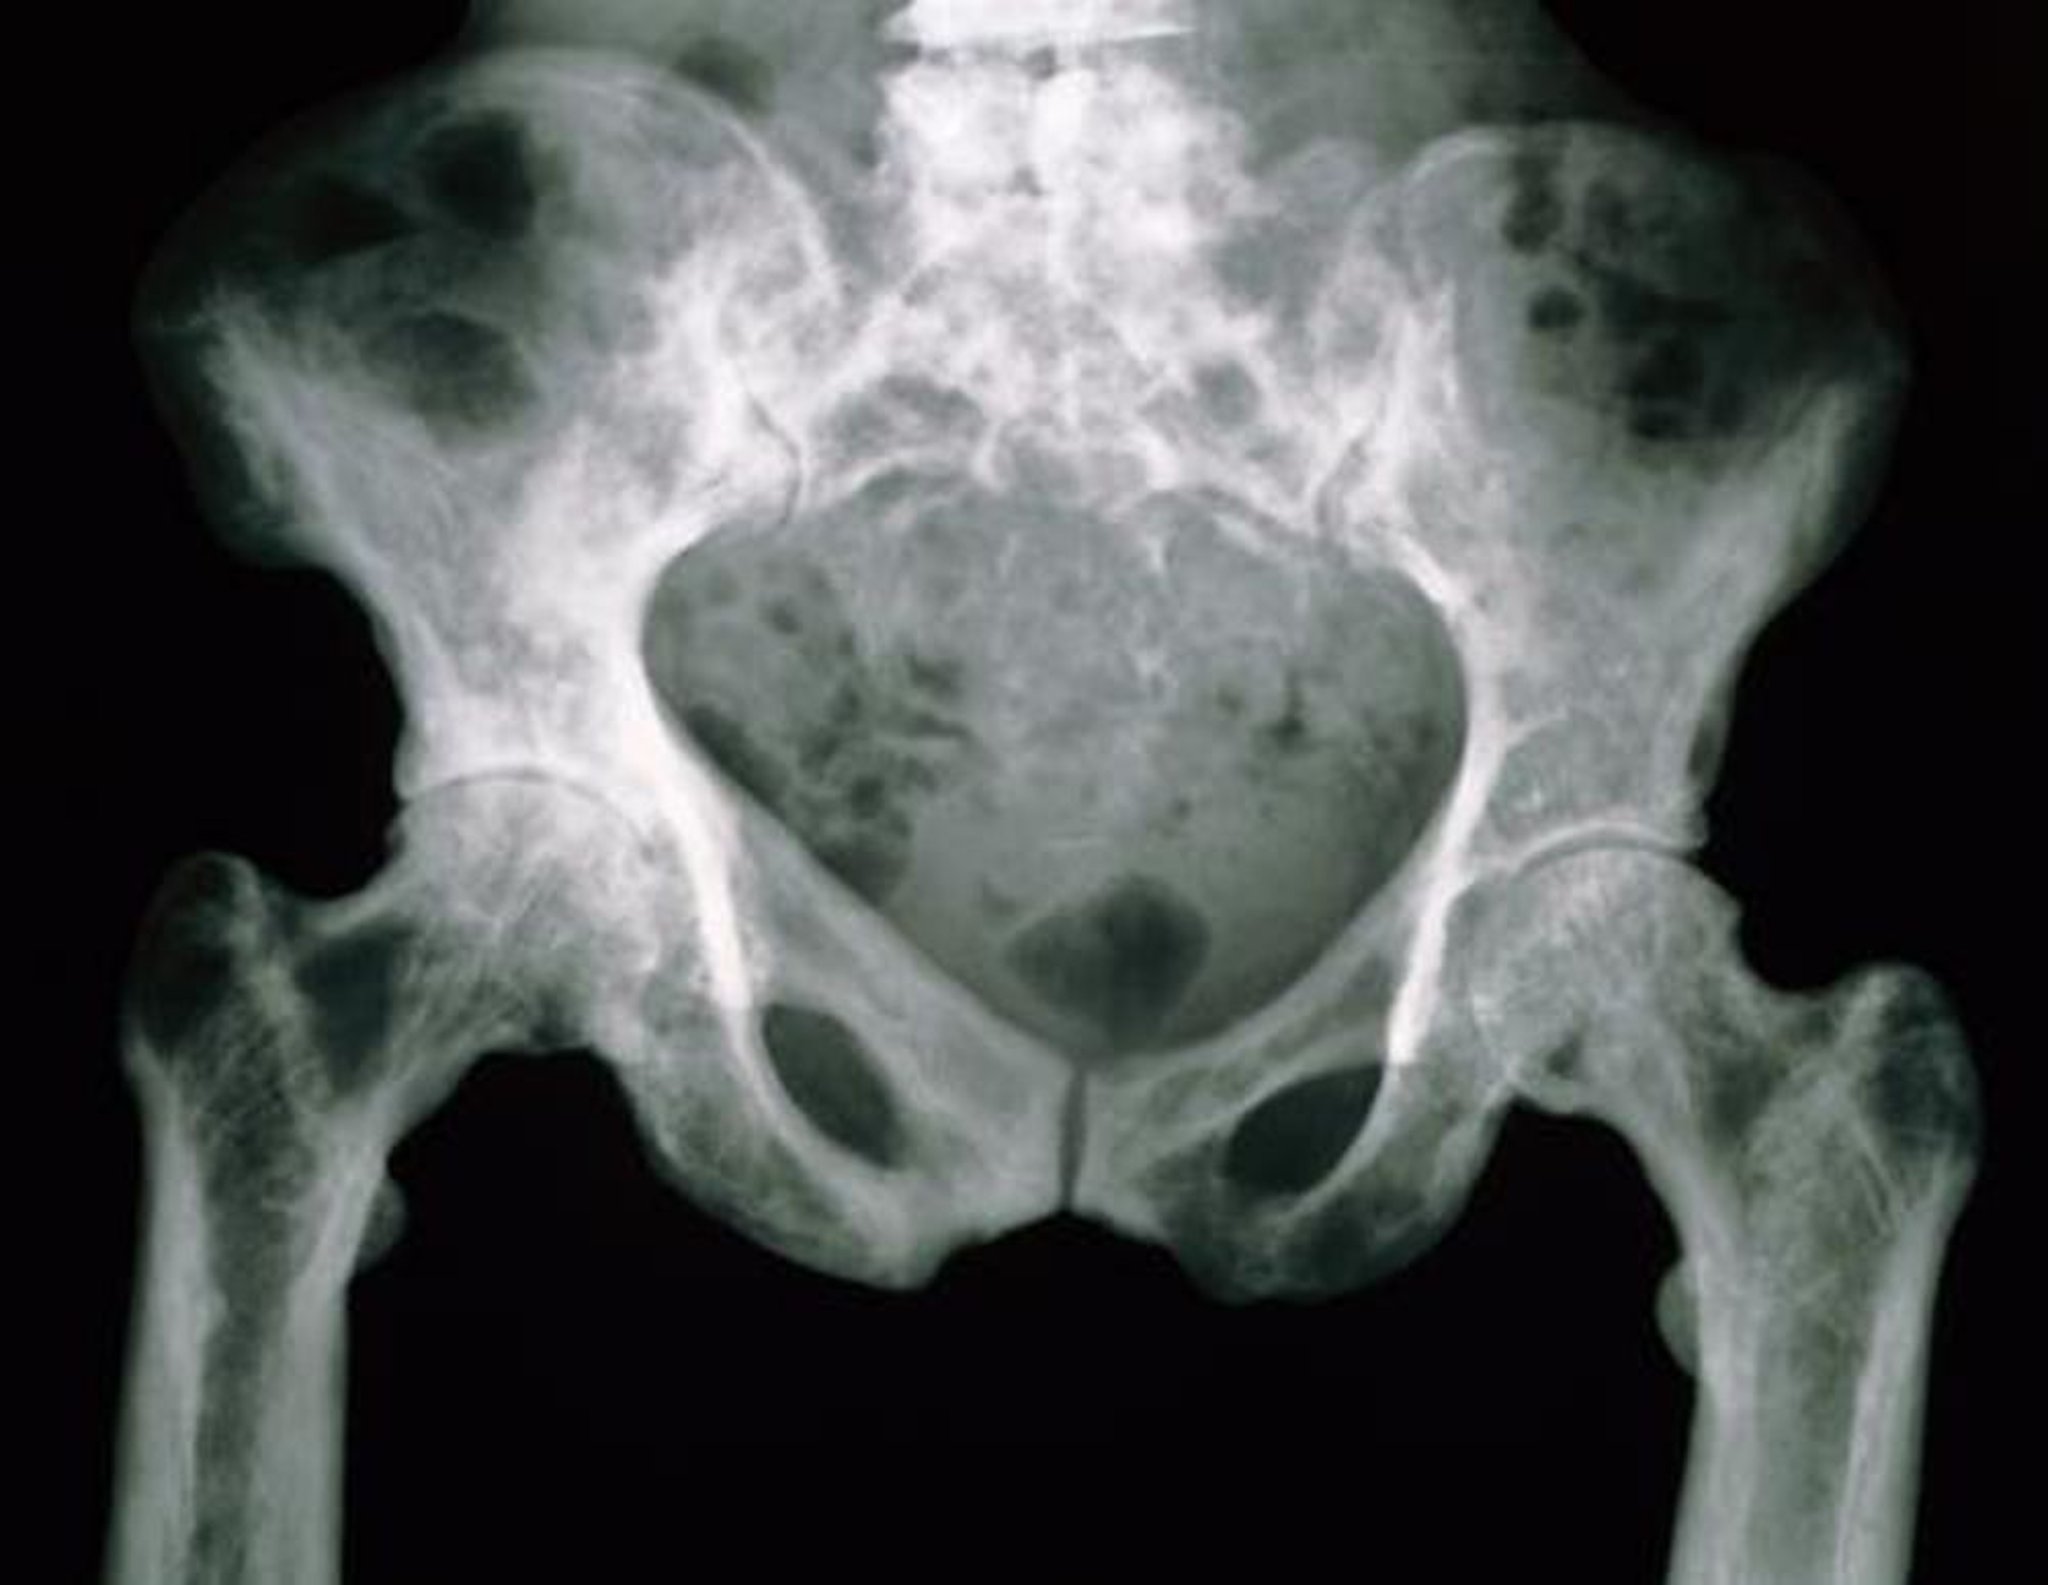

Röntgenaufnahme des Beckens bei Morbus Paget

Die Beckenknochen haben in dieser Röntgenaufnahme aufgrund ihrer erhöhten Porosität ein gesprenkeltes Aussehen.